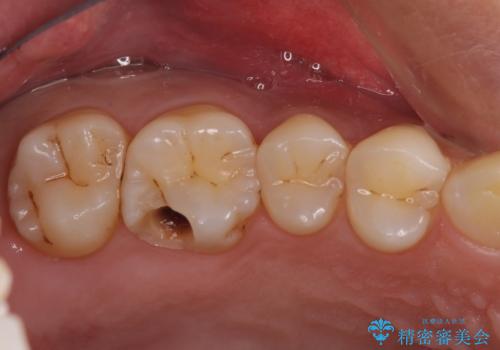

- つめものが欠けたことを主訴にご来院された患者様です。

以前、日本で保険治療をしていましたが、米国滞在中にとれて、仮の再治療をしました。その際に、中に虫歯が残っていると笑われたそうです。

今回は虫歯が大きかったものの、ぎりぎり神経に達しておらず、セラミックインレー(つめもの)の治療のみで完了しました。初診時に虫歯を除去し、後日神経のテストをして正常反応を確認しました。

虫歯を徹底的に除去し、なおかつ神経に達しているかを慎重に判断するには、どうしても顕微鏡&長時間の診療が必要になりますが、保険外治療となります。